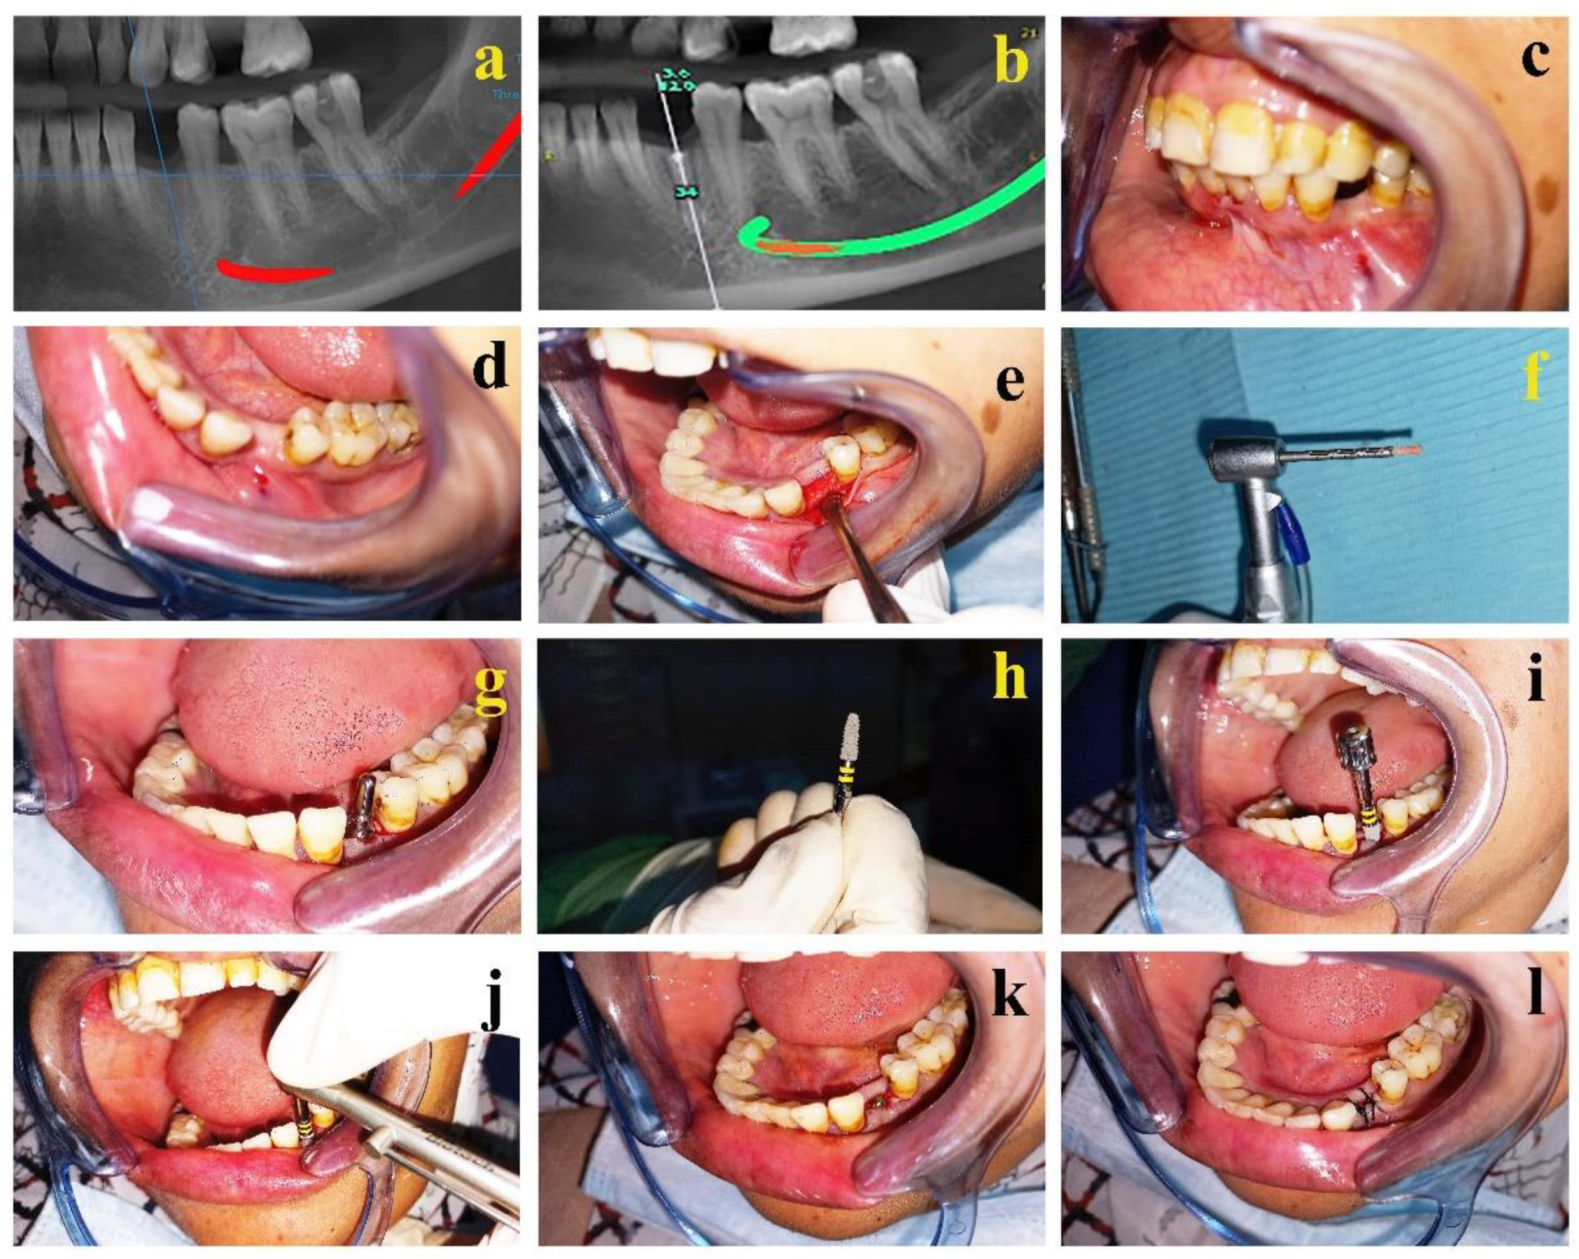

2.18. Implant Placement Surgery

2.19. Measurement of Implant Stability